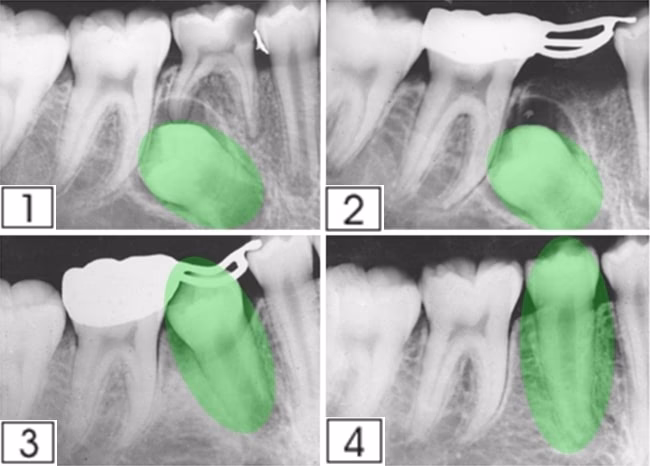

¿Cómo ocultar el espacio en el alambre de ortodoncia?

Algunos ortodoncistas colocan una pieza provisional para ocultar el espacio, y esto se hace generalmente sobre el alambre de ortodoncia. En realidad el tiempo que los espacios permanecen abiertos es relativamente corto por lo que este problema desaparece muy pronto.